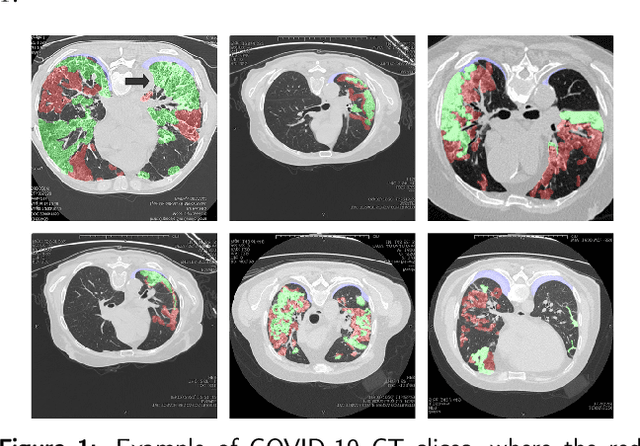

Abstract:The accurate segmentation of multiple types of lesions from adjacent tissues in medical images is significant in clinical practice. Convolutional neural networks (CNNs) based on the coarse-to-fine strategy have been widely used in this field. However, multi-lesion segmentation remains to be challenging due to the uncertainty in size, contrast, and high interclass similarity of tissues. In addition, the commonly adopted cascaded strategy is rather demanding in terms of hardware, which limits the potential of clinical deployment. To address the problems above,we propose a novel Prior Attention Network (PANet) that follows the coarse-to-fine strategy to perform multi-lesion segmentation in medical images. The proposed network achieves the two steps of segmentation in a single network by inserting lesion-related spatial attention mechanism in the network. Further, we also propose the intermediate supervision strategy for generating lesion-related attention to acquire the regions of interest (ROIs), which accelerates the convergence and obviously improves the segmentation performance. We have investigated the proposed segmentation framework in two applications: 2D segmentation of multiple lung infections in lung CT slices and 3D segmentation of multiple lesions in brain MRIs. Experimental results show that in both 2D and 3D segmentation tasks our proposed network achieves better performance with less computational cost compared with cascaded networks. The proposed network can be regarded as a universal solution to multi-lesion segmentation in both 2D and 3D tasks. The source code is available at: https://github.com/hsiangyuzhao/PANet.

Abstract:Coronavirus Disease 2019 (COVID-19) has caused great casualties and becomes almost the most urgent public health events worldwide. Computed tomography (CT) is a significant screening tool for COVID-19 infection, and automated segmentation of lung infection in COVID-19 CT images will greatly assist diagnosis and health care of patients. However, accurate and automatic segmentation of COVID-19 lung infections remains to be challenging. In this paper we propose a dilated dual attention U-Net (D2A U-Net) for COVID-19 lesion segmentation in CT slices based on dilated convolution and a novel dual attention mechanism to address the issues above. We introduce a dilated convolution module in model decoder to achieve large receptive field, which refines decoding process and contributes to segmentation accuracy. Also, we present a dual attention mechanism composed of two attention modules which are inserted to skip connection and model decoder respectively. The dual attention mechanism is utilized to refine feature maps and reduce semantic gap between different levels of the model. The proposed method has been evaluated on open-source dataset and outperforms cutting edges methods in semantic segmentation. Our proposed D2A U-Net with pretrained encoder achieves a Dice score of 0.7298 and recall score of 0.7071. Besides, we also build a simplified D2A U-Net without pretrained encoder to provide a fair comparison with other models trained from scratch, which still outperforms popular U-Net family models with a Dice score of 0.7047 and recall score of 0.6626. Our experiment results have shown that by introducing dilated convolution and dual attention mechanism, the number of false positives is significantly reduced, which improves sensitivity to COVID-19 lesions and subsequently brings significant increase to Dice score.